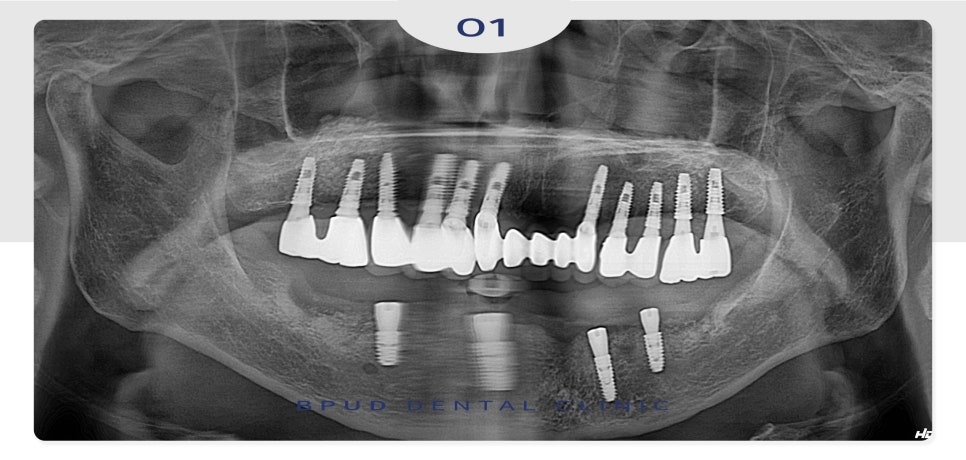

오늘은 임플란트 식립 후

오랜 시간이 지난 뒤, 심한 골소실로 인해

제거 후 재식립을 진행하신 부평역임플란트 환자분을

소개해 드리도록 하겠습니다.

2018.09.18

환자분께서 처음 내원해 주셨을 때,

구강 내 전반적으로 상실된 부위와

심하게 충치가 진행된 부위를 발치하고

전체적으로 임플란트 식립을 진행하였는데요.

2024.07.09

환자분의 사정상,

오랫동안 미루고 미루다 잇몸이 불편해져

약 6년 뒤 내원하셨을 때는

이미 양쪽 아래 어금니 부위와 앞니에

심한 골 소실이 진행되어 신경관까지의 거리가

3mm 정도 남아 제거가 필요한 상태였는데요.

따라서 전체적인 치주치료와

기존 임플란트 제거 후 재식립을 설명드렸습니다.

2024.08.07

하지만 또 방치를 하시다가

한 달 후에는 결국 임플란트와 보철이

통째로 빠지셔서 내원해 주셨는데요.

자녀분들과 함께 내원하셔서

전체적인 설명을 충분히 드리고

제거 후 재식립을 진행하기로 하였습니다.

2024.08.12

수술 진행을 위해 잇몸을 열었을 때

잇몸에 완전히 묻혀 있어야 할

인공치근의 나사선들이 잇몸 위로

모두 드러나 있는 상태였습니다.

남겨서 사용할 수 있는 임플란트는

사용하기로 하셨지만 판단 결과

모두 다 제거하는 것이 맞다고 판단되어

식립 진행하였습니다.